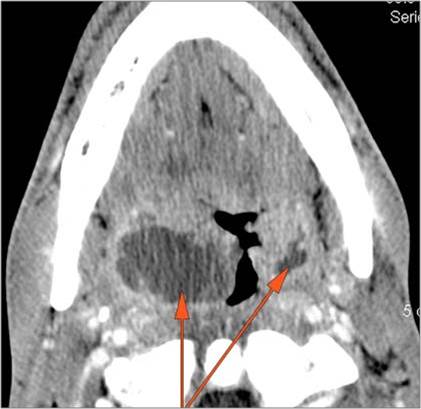

There is excessive enhancement or thickening of the fat or other soft tissues within or surrounding the buccal space, masticator space, floor of the mouth, submandibular space or the adjacent superficial fascia or subcutaneous fat and skin. [Yes/No]

There is subperiosteal abscess or an abscess cavity adjacent to or involving the maxilla or mandible. [Yes/No]

The lingual or buccal aspect of the mandible is eroded. [Yes/No]